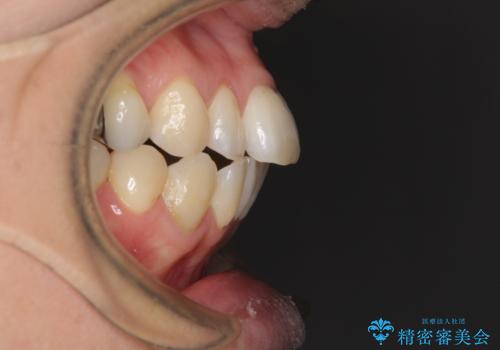

歯列不正は軽微であったため、インビザライン・ライトにて改善することとしました。

左下大臼歯は根管治療が必要であったため、矯正治療前に根管治療を行い、その後矯正治療を行うこととしました。

矯正治療後には期にある銀歯を全てセラミッククラウンなどで補綴治療することとしました。